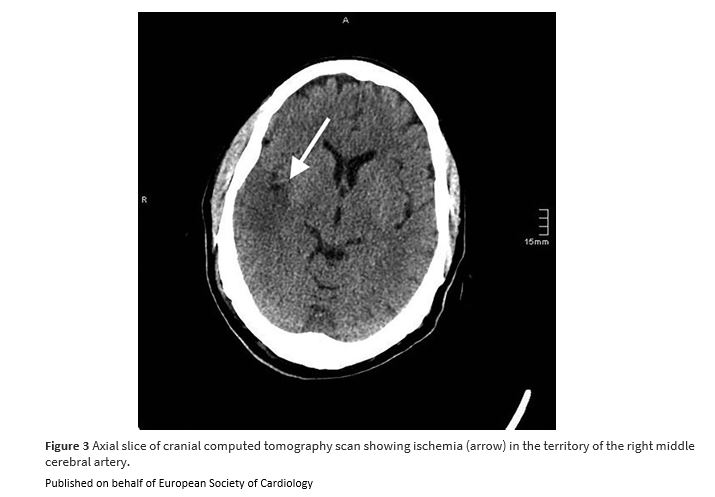

Unexpected paradoxical embolisation following catheter-directed thrombectomy with the FlowTriever™ system in a case of pulmonary embolism bit.ly/41n1RlZ

#EHJCaseReports #EchoFirst @aayshacader @KardiologieHH @ANazmiCalik @EHJCREiC @TJ_Yeo @Phiso_de @FarhanaAra